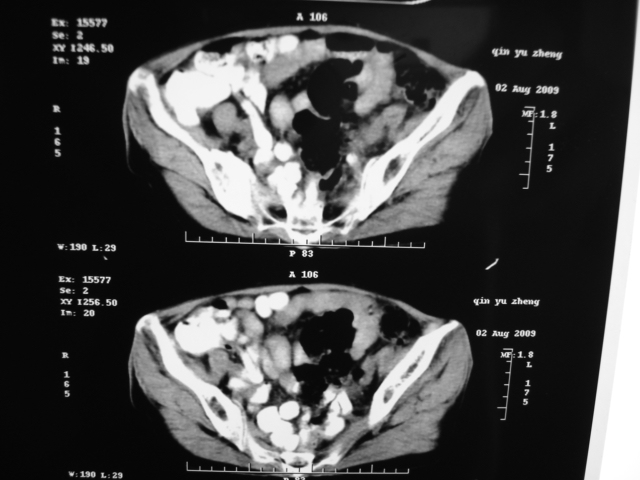

同事奶奶,73岁,腹痛一年,夜晚较重,潜血+++,拒绝增强,考虑左肾ca并腹膜后转移;请各位老师帮忙看看,谢谢!

左肾癌侵及输尿管上段,腹膜后多发淋巴结转移,脾脏钙化灶。至于潜血+++,要考虑消化道病变,本次ct片肠腔未见明显异常。

1)考虑左肾癌侵犯肾盂并腹膜后淋巴结转移。2)脾脏钙化灶。

考虑左肾癌侵犯肾盂并腹膜后淋巴结转移。